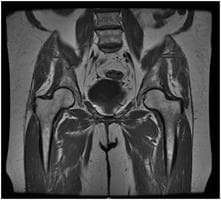

Get rid of your pain with Hip MRI! Fast and reliable MRI imaging service with expert radiologists. Early diagnosis, healthy life!